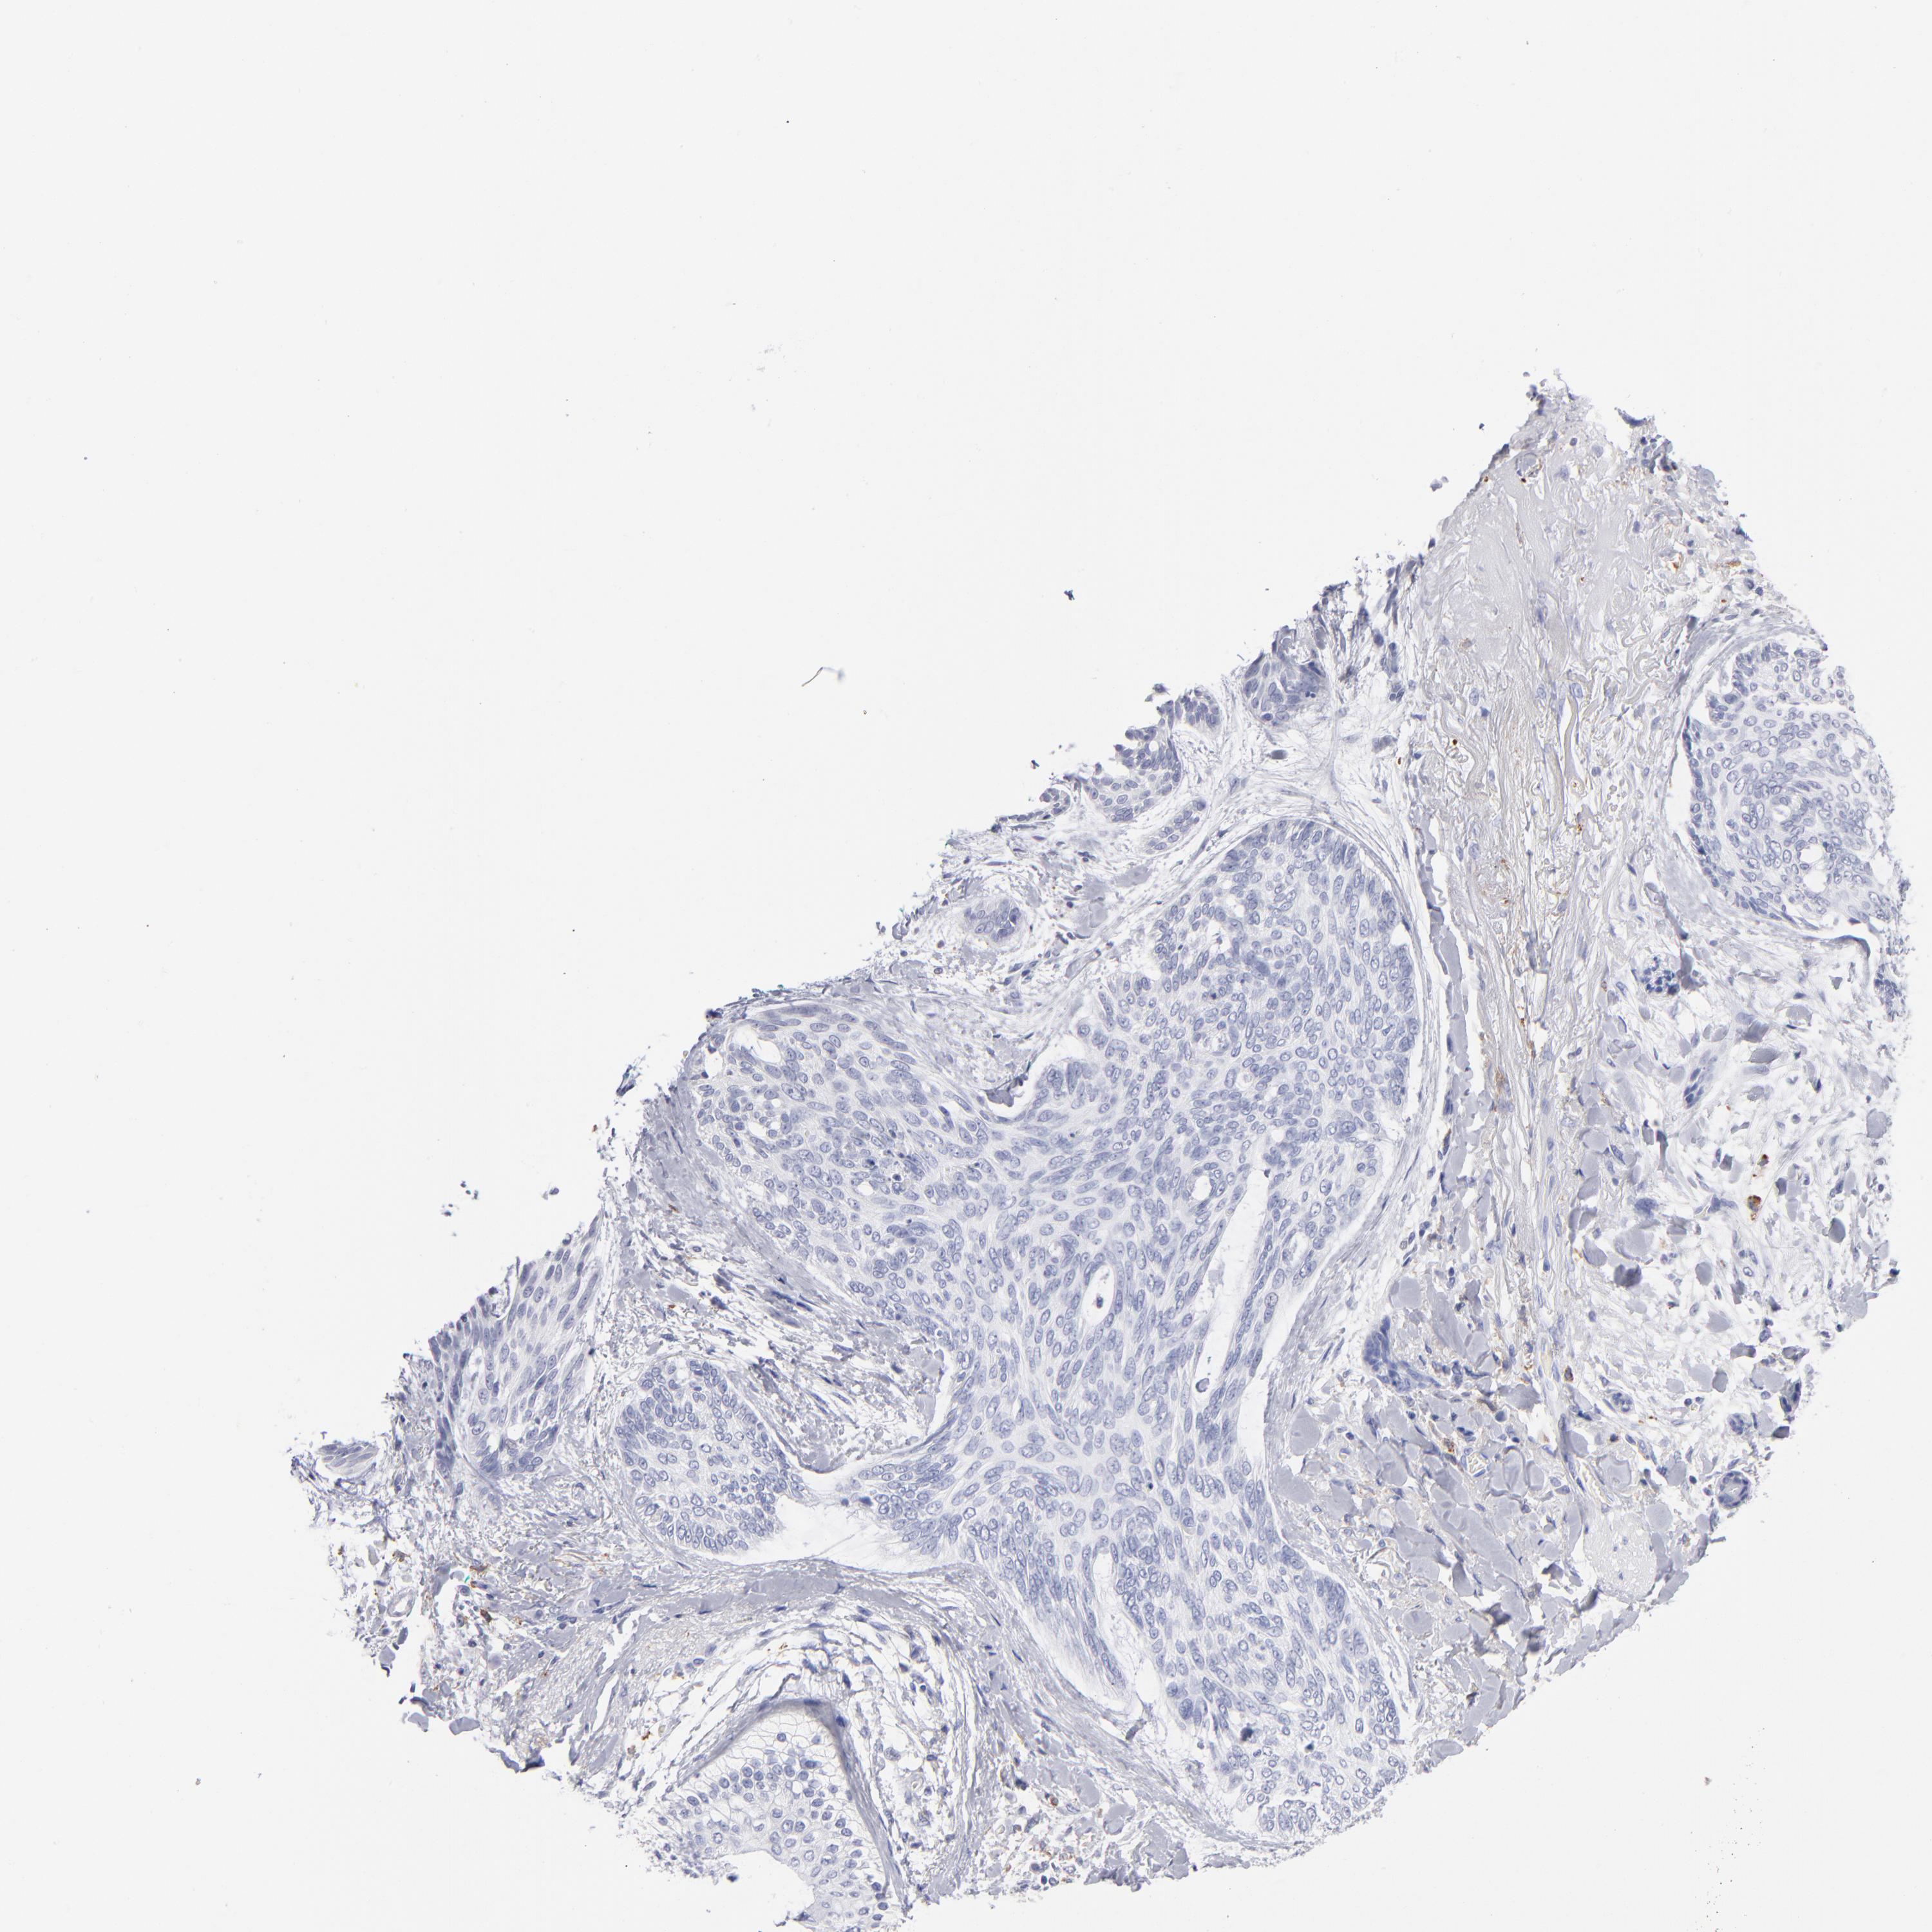

CANCER SKIN CANCER Show tissue menu

SKIN CANCER - Protein expressioni

A mouse-over function shows sample information and annotation data. Click on an image to view it in a full screen mode. Samples can be filtered based on level of antibody staining by selecting one or several of the following categories: high, medium, low and not detected. The assay and annotation is described here.

Each image is clickable and will lead to virtual microscopy that enables deeper exploration of all samples and also displays staining intensity scores, fraction scores and subcellular localization as well as patient and tissue information for each sample.

Antibody HPA003740

Staining

High

Medium

Low

Not detected

Intensity

Strong

Moderate

Weak

Negative

Quantity

>75%

75%-25%

<25%

None

Location

Nuclear

Cytoplasmic/membranous

Cytoplasmic/membranous,nuclear

Squamous cell carcinoma, NOS

Basal cell carcinoma